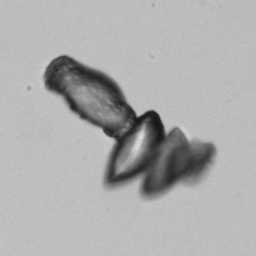

Uric acid - Irregular

Uric acid crystals occur with increased uric acid excretion or in acidic urine (pH < 5.8). Uric acid is a waste product of purine metabolism; purines are chemical compounds such as adenine and guanine (DNA components), caffeine and xanthine, and are mainly found in meat (products). The crystals can take various forms: usually diamond- or diamond-shaped plates, hexagonal plates, cylindrical structures (barrels), elongated prisms, star-shaped, spherical, needle-shaped or dumbbell-shaped crystals. They are usually yellowish to brown in color and show strong, polychromatic birefringence. They may precipitate when the urine has been kept cold prior to analysis.

The yellow discoloration of the crystals in this preparation is caused by fixation with glutaraldehyde.